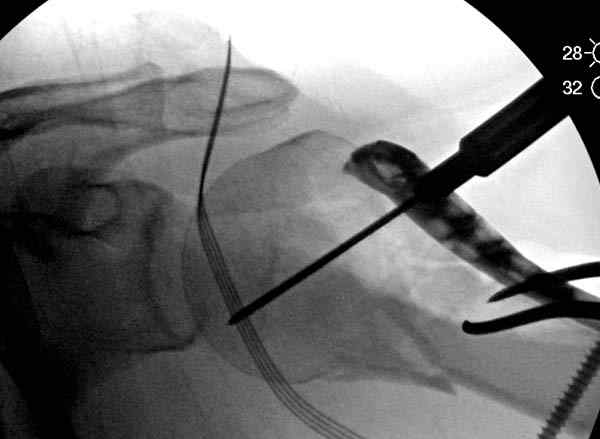

Здесь пример открытой репозиции 57 летнего с переломом плеча (1,2) смещение обнаружено на интероперационном снимке. При нормальной прямой проекция (3) угловое смещение обнаружили в аксиальной проекции (4)

После устранения смещения пластина установлена выше (5,6,7) и финальные снимки (8,9,10)

Подбор импланта тоже имеет значение, например многие импланты направлены для фиксации перелома без учета ротаторной манжетки. Предпочтительными являются низко сидящие полиаксиальные пластины, где верхние шурупы можно проводить под углом в 120 градусов. (11)

Пластина от Synthes или ее копии (надеюсь простят критику друзья из Деоста) считаются трудным из-за обширности доступа, особенно при установке верхне-заднего шурупа, где доступ надо расширять в верхнем отделе до ротаторной манжетки. Верхне сидящие импланты предназначены для проведения опоры (buttress) за бугристость плеча, но тогда приходится сталкиваться с подакромиальным импинжментом.